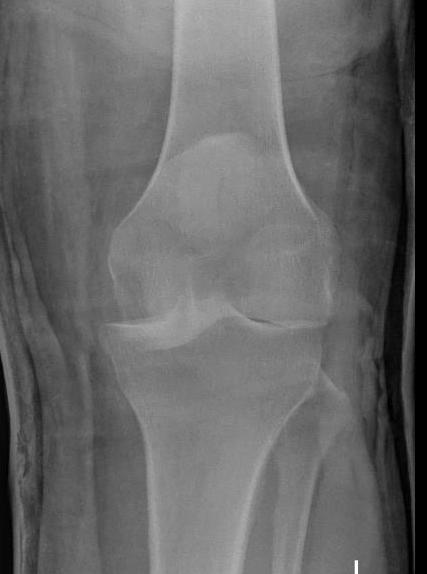

Complete knee dislocation, compound, KDIV

Obvious ligamentous laxity

Excessive recurvatum Grade 3 Lateral laxity